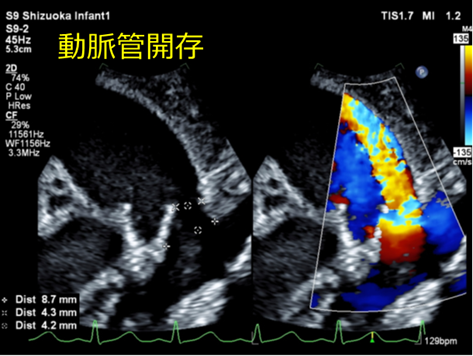

動脈管開存(PDA)とは

胎生期の動脈管が閉鎖せず大動脈肺動脈間の血行路として残存している状態のこと。

短絡量が多いと心不全症状を引き起こします。